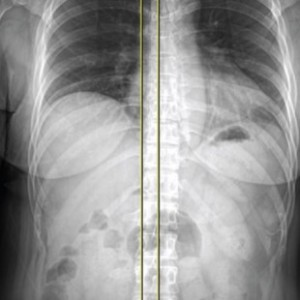

척추

척추측만증 또는 한쪽으로 기울어진 척추로 인해 체중이 한쪽 무릎에 집중된다면 장기적으로 기울어진 쪽 무릎에 관절염이 빠르게 진행됨

▲ 무릎 수술환자의 스캐노그램 엑스레이 검사